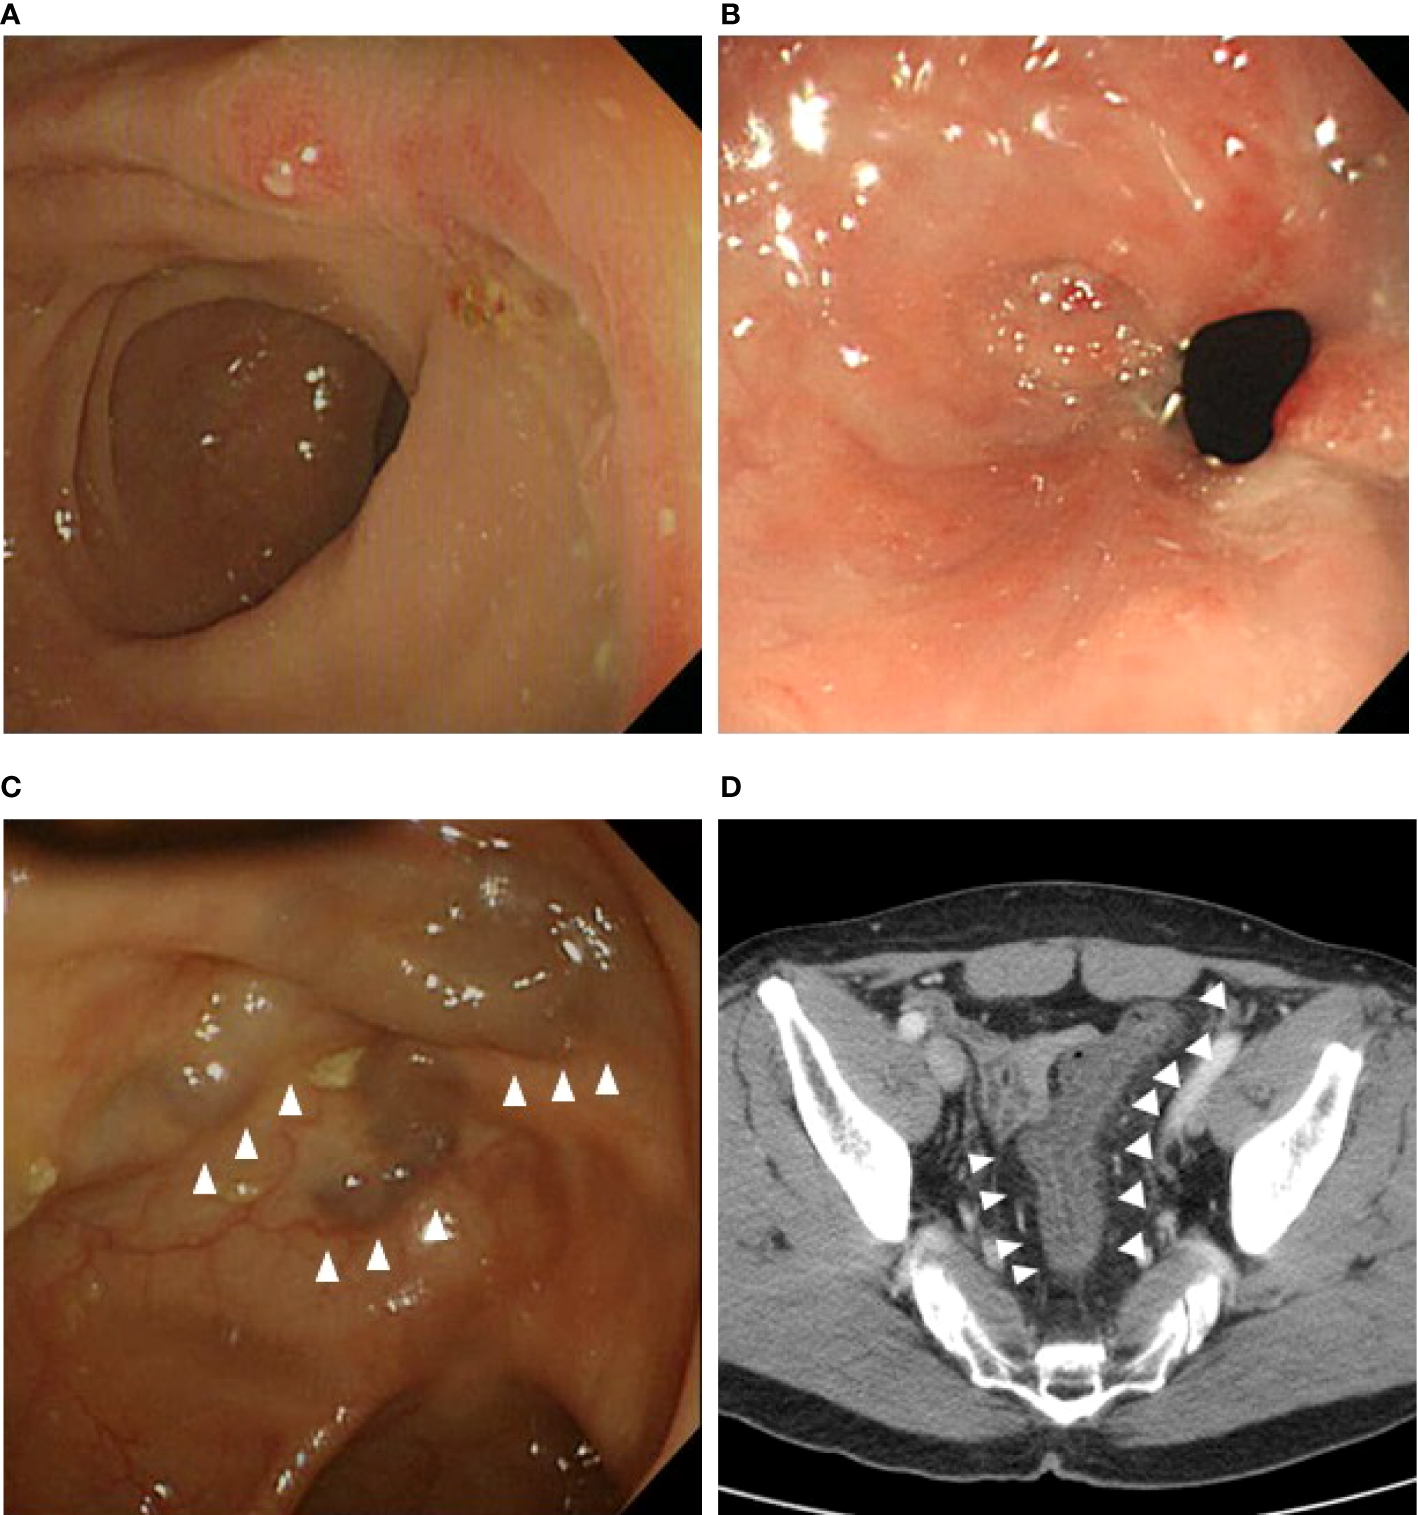

We investigated the postoperative intestinal complications, and the proportion of patients with postoperative complications was compared between those who underwent IMV preservation and those who underwent ligation. We defined intestinal complications as ulceration, stricture, venous engorgement, and colitis in the remnant colon and confirmed these using computed tomography (CT) or colonoscopy. Previous diagnoses of inflammatory bowel disease with involvement of other intestinal sites were not counted. CT and endoscopic findings were confirmed by reviewing the medical records of those who underwent regular postoperative examinations. An anastomotic ulcer was defined as mucosal breakdown localized solely to the anastomotic site observed via colonoscopy (Figure 2A) (21). Anastomotic strictures were present if (1) significant force was required to pass the colonoscope beyond the anastomosis and this produced visible trauma after passing through, and/or (2) balloon dilation was required for passage of the colonoscope to visualize the remainder of the colon (Figure 2B) (21). Venous engorgement of the remnant distal stump was defined as prominent enlarged veins and varices on CT or colonoscopy (Figure 2C) (21). Colitis of the remnant distal stump, caused by inadequate venous circulation, ranging from mild mesenteric panniculitis to severe congestive ischemic colitis requiring surgery, was diagnosed using CT and colonoscopy (Figure 2D) (3, 22–25).

Figure 2

Intestinal complications on computed tomography or colonoscopy during follow-up. (A) Anastomotic ulcer. (B) Anastomotic stricture. (C) Venous engorgement at the remnant distal bowel. (D) Colitis with thickened colon wall at the remnant distal bowel.